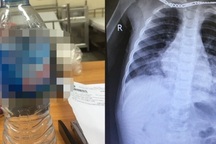

Xuất huyết tiêu hóa là một bệnh hiếm gặp ở trẻ sơ sinh (Ảnh minh họa: Stocksy United).